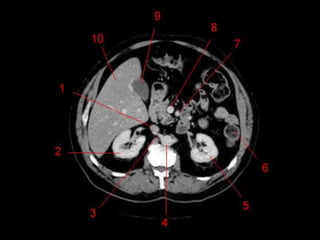

Subdivisão Funcional

• Os oito segmentos são divididos:

– A primeira divisão é realizada dividindo através da

Porta Hepática, em esquerdo (I a IV) e direito (V a VIII)

– A divisão é feita baseada em um relógio

– Caudado é o segmento I

– No ‘lobo’ esquerdo, o IV separa-se do II e do III pela

veia hepática esquerda, representado

anatomicamente pelo ligamento falciforme.

– II e III se dividem através de uma linha imaginária

transversal na altura da porta hepática.

– No ‘lobo’ direito, se divide os segmentos através de

uma linha transversal e pela veia hepática direita.

Subdivisão Funcional • Osoito segmentos são divididos: – A primeira divisão é realizada dividindo através da Porta Hepática, em esquerdo (I a IV) e direito (V a VIII) – A divisão é feita baseada em um relógio – Caudado é o segmento I – No ‘lobo’ esquerdo, o IV separa-se do II e do III pela veia hepática esquerda, representado anatomicamente pelo ligamento falciforme. – II e III se dividem através de uma linha imaginária transversal na altura da porta hepática. – No ‘lobo’ direito, se divide os segmentos através de uma linha transversal e pela veia hepática direita.